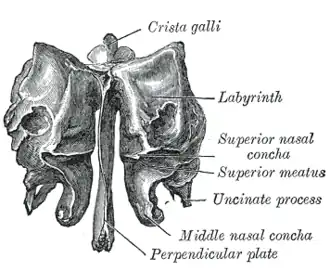

Visto de cima.

Visto de cima. Placa perpendicular ao etmoide.

Placa perpendicular ao etmoide. Visto pelo lado direito.